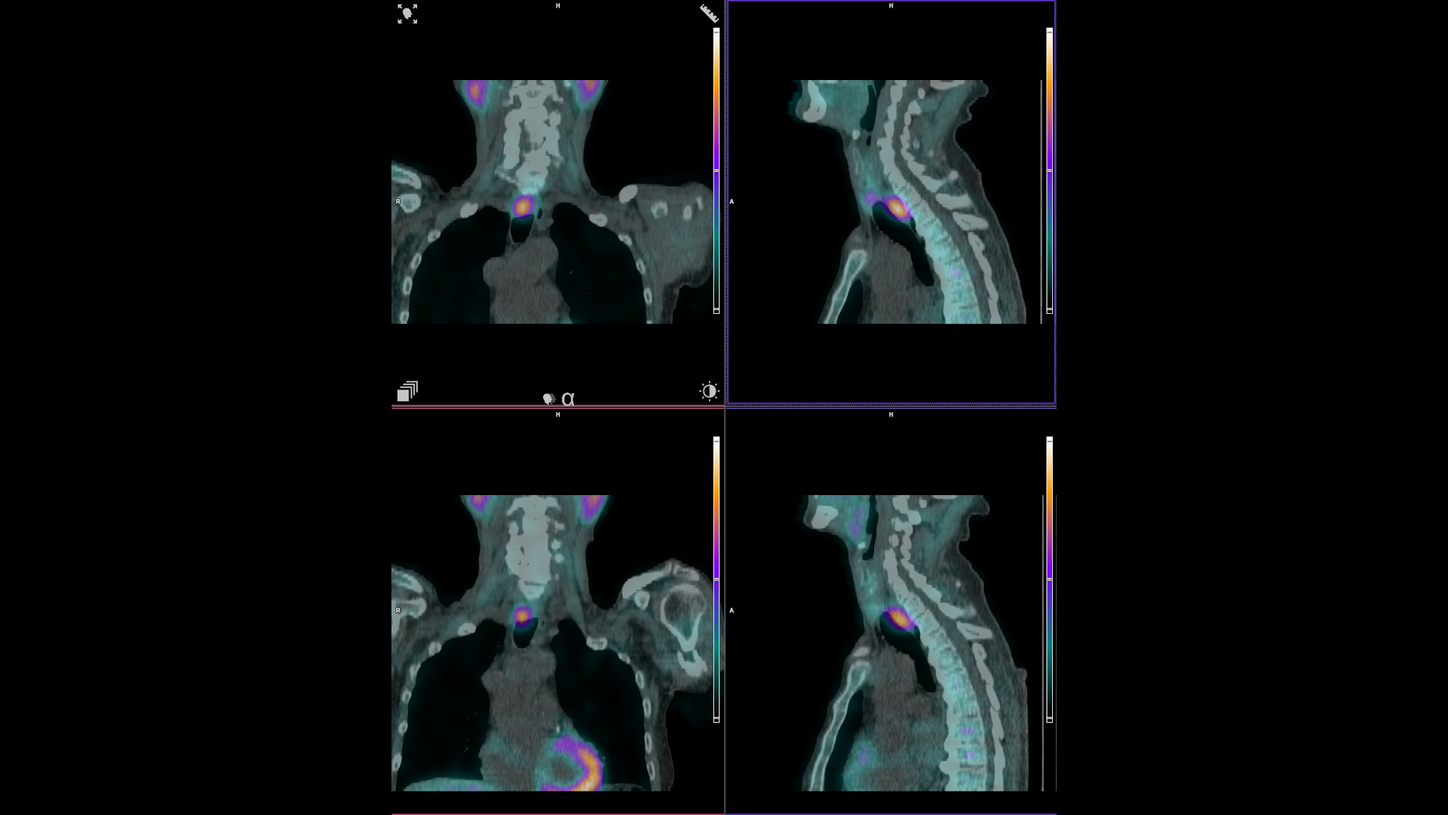

The nuclear medicine team now routinely uses SPECT/CT for cardiac attenuation correction, parathyroid localization, infection imaging for prosthetic joints, and skeletal assessments. This expansion has led to increased throughput, greater scheduling flexibility, and the ability to combine multiple imaging studies more efficiently.听

鈥淧reviously, four to five parathyroid scans could be performed in one 8-hour shift, without the possibility of other scans,鈥 explains Koutsikos. 鈥淣ow, with Symbia Pro.specta鈥檚 enhanced workflow capabilities, we can efficiently manage more studies leading to increased patient throughput, including complex procedures like myocardial perfusion and parathyroid imaging.鈥澨

The team still regularly uses conventional planar imaging for specific applications, such as renal or thyroid studies, but most complex cases now move directly to SPECT/CT, when necessary, enhancing both diagnostic confidence and clinical decision-making.

鈥淥ur referring physicians immediately noticed the difference,鈥 Koutsikos says. 鈥淭hey were impressed by the anatomical detail and localization capabilities that hybrid imaging provides.鈥